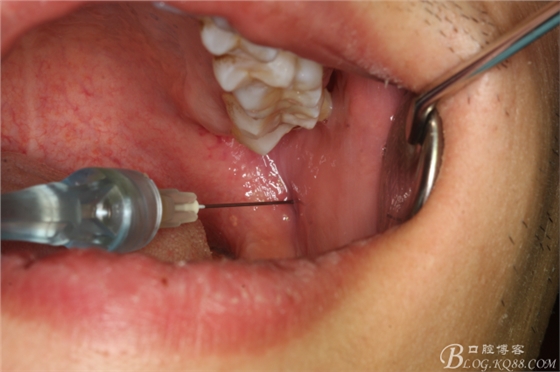

圖3 行下牙槽神經(jīng)無(wú)痛阻滯麻醉